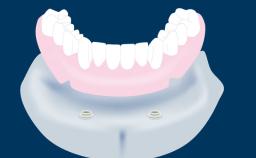

Fixed and removable prosthodontic implant therapy for restoration of the edentulous maxilla is both complex and challenging. Careful assessment and planning is needed in each individual case to explore whether a fixed or a removable solution will be the more suitable to satisfy the patient’s preference for optimal esthetics, phonetics, comfort and function. This Learning Pathway explores the prosthodontically driven treatment planning based on structured assessment, considered diagnosis and practical application in clinical case examples.